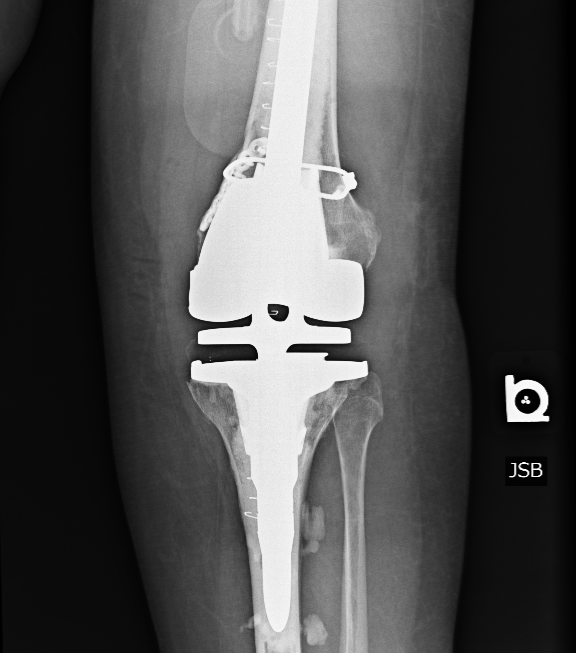

Mrs. Fitch would have to go through another procedure to both fix the fracture but also replace the original implant. She underwent a revision total knee replacement with an open reduction internal fixation (ORIF) of the fracture, as well as a hinged knee prosthesis to replace her prior knee replacement implants. The post-operative X-Ray shows the difference in implant, as well as a stabilized fracture: